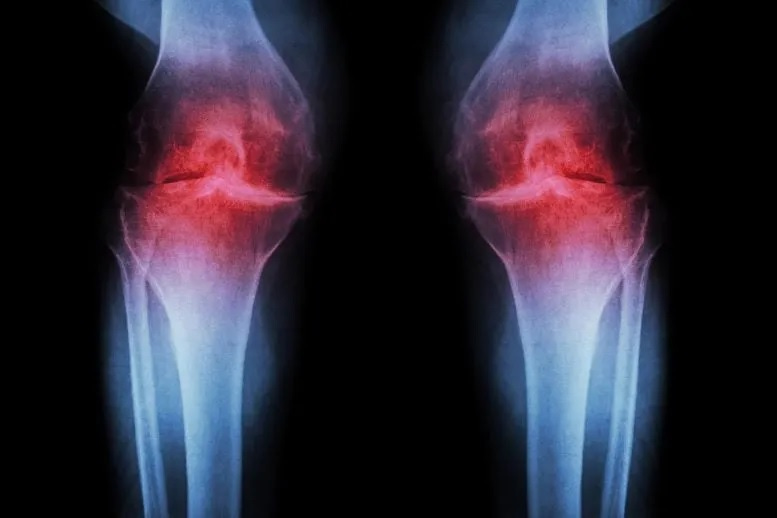

It’s a common story these days: An active person works hard and saves for a retirement that, they expect, will feature hiking, biking, and tournament-level pickelball. But when the big day arrives, so does multi-joint osteoarthritis, which makes most of the above prohibitively painful.

Rather than easing symptoms, the treatment works by addressing the underlying driver of osteoarthritis. This degenerative joint condition affects roughly one in five adults in the United States and generates an estimated $65 billion in direct health care costs each year. At present, no available medication can halt or reverse the disease, leaving pain management and joint replacement as the primary treatment options.